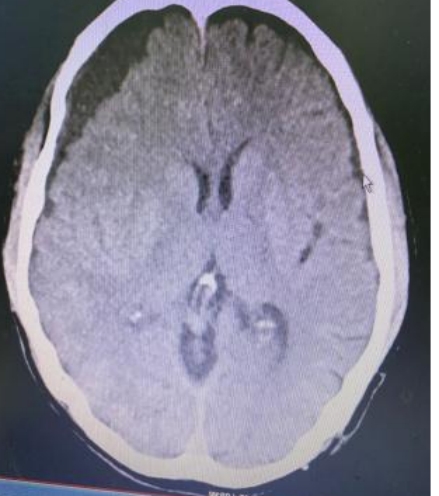

术后

附二医院副院长赵正据了解情况后将患者收治到外一科,管床医生张胜伟详细查体及询问病史后,完善头部CT、MRI等检查,推翻了之前“颈椎病”的诊断,更改诊断为“亚急性硬膜下血肿伴脑疝形成”。赵正据教授考虑到患者年龄大,基础疾病多,病情紧急,迅速组织医生急诊采用微创技术为患者进行治疗。术中,张胜伟医生精细操作,手术切口长度仅4cm,术中出血不到10ml,手术时长不到1小时。护理团体严密观察术后患者的生命体征、意识、肌力、肢体感觉等,做好引流管的护理及相关健康知识宣教。术后患者言语清晰,肢体活动正常,动态复查头颅CT显示颅内血肿清除效果良好,术后1周即顺利出院。患者为表示感谢,特为科室医护送上“医术精湛,尽职尽责”的锦旗。